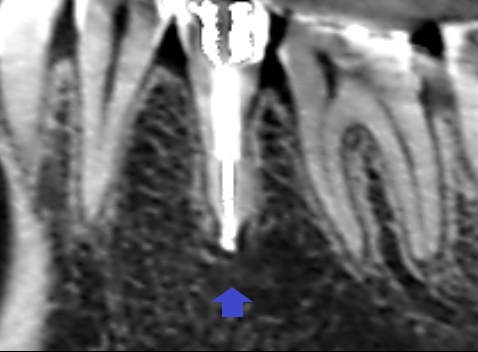

精密根管治療6カ月後の経過観察時の矢状断のCT画像です。下顎第二小臼歯の矢印の先にあった膿の影が消え、歯槽骨が再生しています。

精密根管治療6カ月後の経過観察時の冠状断のCT画像です。下顎第二小臼歯の根の舌側に拡がっていた膿の影が消え、歯槽骨が再生しています。